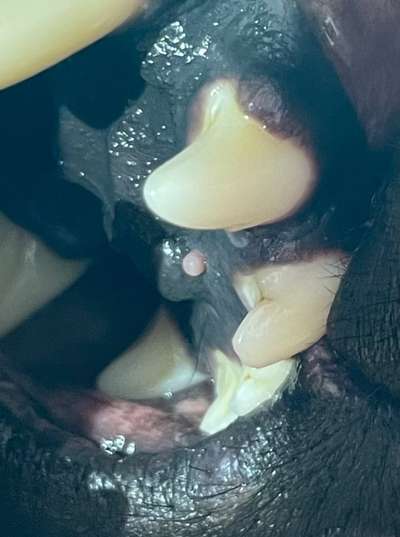

Hallo zusammen, keine Sorge- ein Tierarzttermin wurde schon vereinbart. Mich würde allerdings interessieren ob bemand sowas schon mal gesehn hat. Hab bei meinem Liebling gestern diese Zubildung am harten Gaumen gesehn (neben dem Jakobschen Organ) hat jemand eine Idee was das sein kann? (Ein Epulide könnte es sein- zumindest von der Art des Gewebes her- nur der Ort dafür ist komisch. Vielen Danke schon mal. Und Grüße

Wie du schon schreibst. Epulide treten meistens am Zahnhalteapparat auf. Vielleicht eine Wucherung die durch einen Virus ausgelöst wurde? Sollte schnell beim TA abgeklärt werden.

Also waren beim Tierarzt, ist wohl en Epulide- können überall an der Mundschleimhaut kommen ist halt nur seltenn dass es an dieser stelle ist…

Im Mai muss unsre Madame eh wieder zum Impfen da wirds dann nochmal angeschaut(Veränderung)